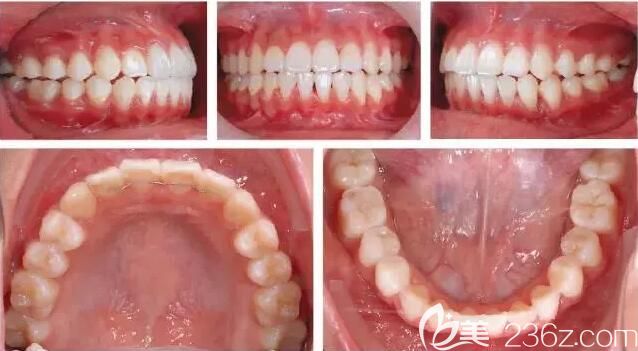

治療后效果展示

牙根排列理想,牙列擁擠、歪牙得到改善。

矯正后面容改變